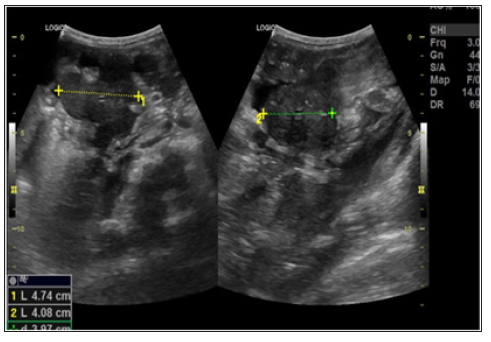

Patient started treatment with amphotericin B and after 15 days performed a new ultrasound of the abdomen to control treatment that showed persistence of lymph node enlargement near to the pancreas body, reduction of ascites, with a small amount of free fluid in the pelvic cavity, and a volumetric reduction of the linfonodal mass, located on the right flank measuring 4.7 x 4.0 cm (Figure 6). During the 41 days of hospitalization, the patient remained hemodynamically stable, presenting febrile peaks attributed to the intercurrence of infectious condition caused by K.pneumoniae and S.hominis being treated with cefepime and vancomycin. There were bilaterally microadenomegalies in the posterior cervical chain and right axillary adenomegaly, mobile, painless and elastic, with no other conditions. Patient evolved with clinical, laboratory and radiological improvement followed by hospital discharge.

Figure 6: USG performed 15 days after starting treatment showing a volumetric reduction of lymph node mass in the right flank.